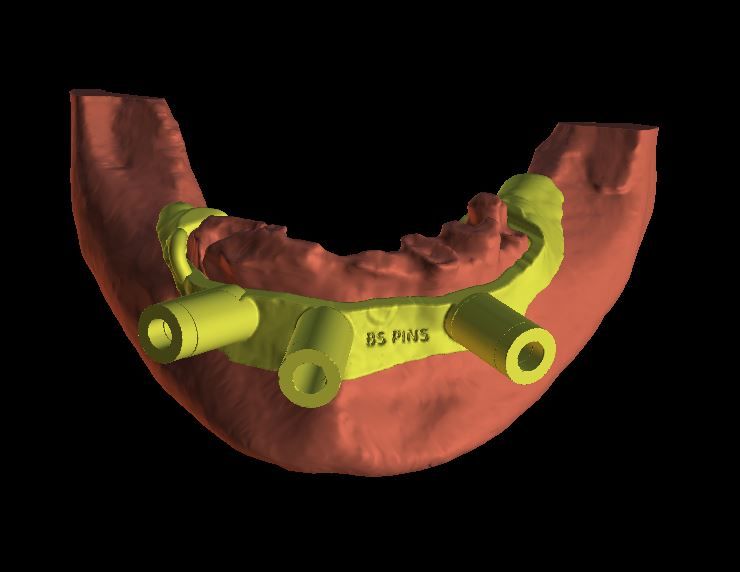

- Learn to create a surgical guide for $20 that can be printed in your office or outsourced to a commercial printer for less than $50

- Learn the scanning protocols needed to do any type of surgical guides, how to do them and when to use each one

- Get very proficient with tooth supported and tissue supported surgical guides